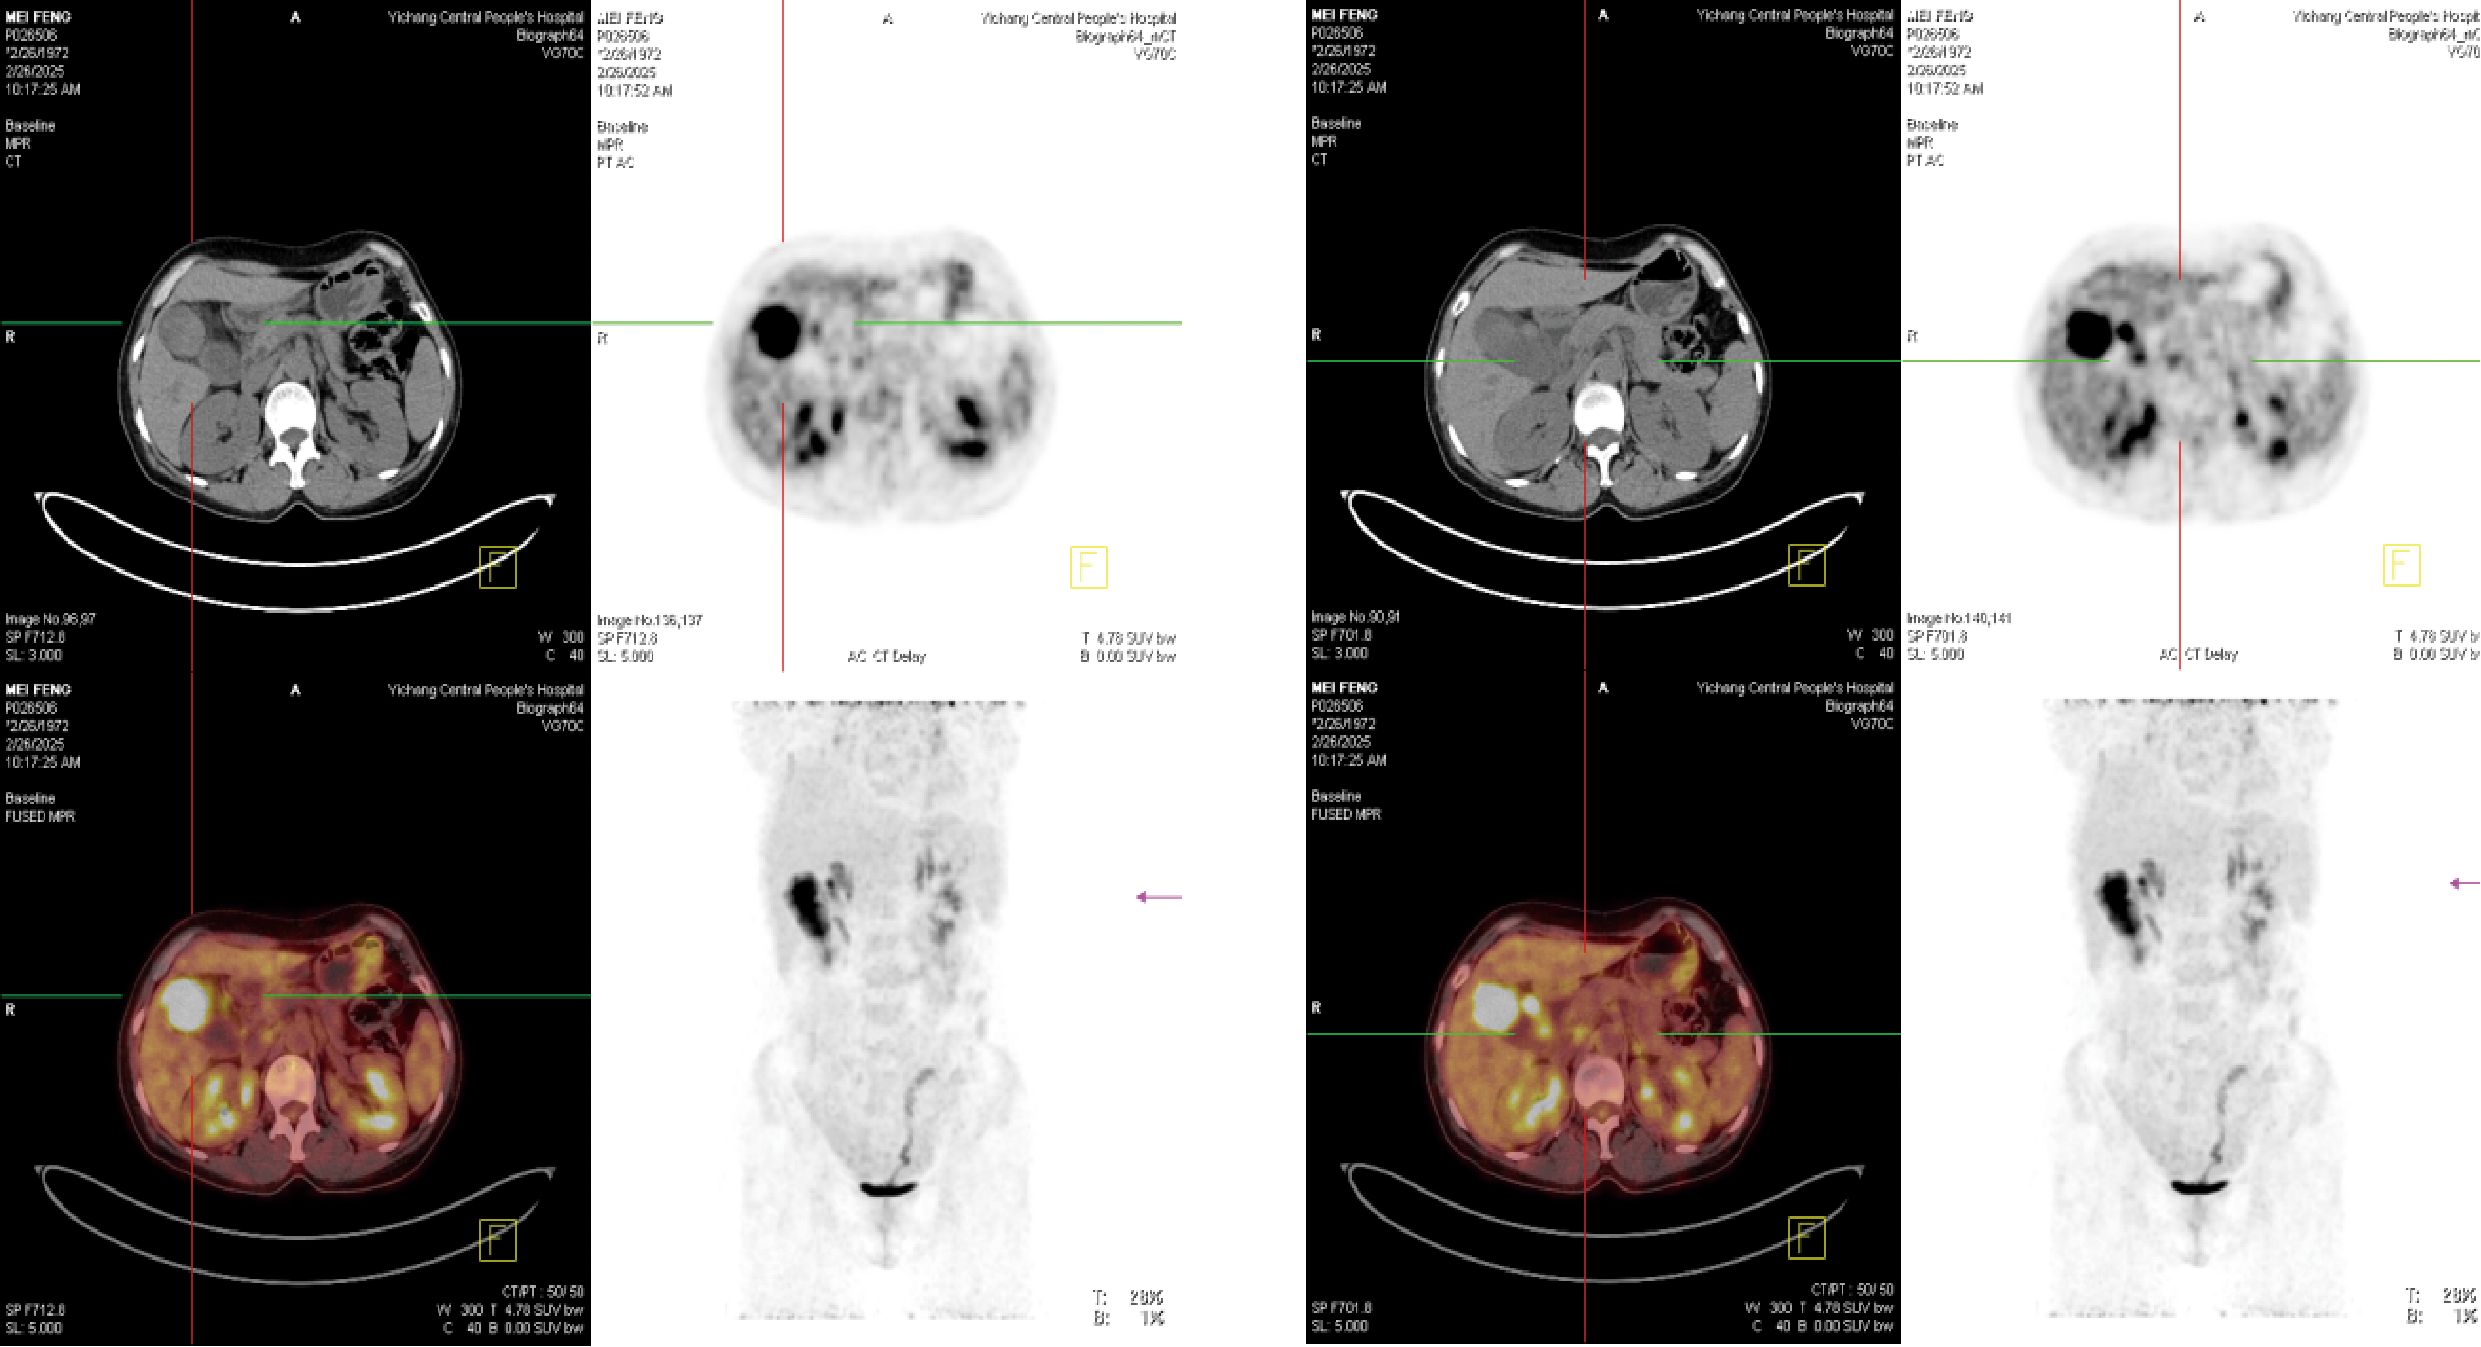

To further clarify the nature of the gallbladder mass, abdominal color Doppler ultrasound, upper abdominal contrast-enhanced CT, and PET-CT examinations were performed. Ultrasound revealed an enlarged gallbladder measuring approximately 9.7 × 4.2 cm with a moderately echogenic nodule filling its lumen, of indeterminate nature (See Figure 1). Contrast-enhanced CT showed increased gallbladder volume with localized uneven wall thickening and soft tissue density nodules protruding into the lumen, strongly suggesting neoplastic growth (Figure 2). Multiple nodular shadows were observed in the hepatic portal region, likely representing enlarged lymph nodes, with the largest measuring 1.9 × 1.7 cm. PET-CT confirmed increased retroperitoneal lymph nodes with elevated SUVmax values of approximately 18.0 and 25.9 on early and delayed imaging, respectively (Figure 3). These findings, showing both gallbladder soft tissue nodules and enlarged lymph nodes with abnormal metabolic activity, led to a preoperative diagnosis of gallbladder carcinoma with hepatic portal lymph node metastasis.

Ultrasonographic images of the gallbladder.(A) The gallbladder is enlarged, measuring approximately 9.7 x 4.2 cm, with a non-thickened wall. Multiple hyperechoic foci are seen within the lumen, accompanied by dense posterior acoustic shadowing.(B) Two medium-echoic masses, measuring approximately 7.0 x 3.1 cm and 2.3 x 1.4 cm respectively, are seen filling the gallbladder. A separate medium-echoic nodule, measuring approximately 1.4 x 1.0 cm, is attached to the gallbladder wall. This nodule shows no posterior acoustic shadowing and does not move with changes in patient position. The biliary system is not dilated.

Figure 1. Ultrasonographic images of the gallbladder. (A) The gallbladder is enlarged (measuring approximately 9.7 × 4.2 cm) with a non-thickened wall (delineated by dashed line). Multiple hyperechoic foci are observed within the lumen, accompanied by dense posterior acoustic shadowing. (B) A medium-echoic mass, measuring approximately 7.0 × 3.1 cm, is visible within the gallbladder lumen (outlined by dashed line).